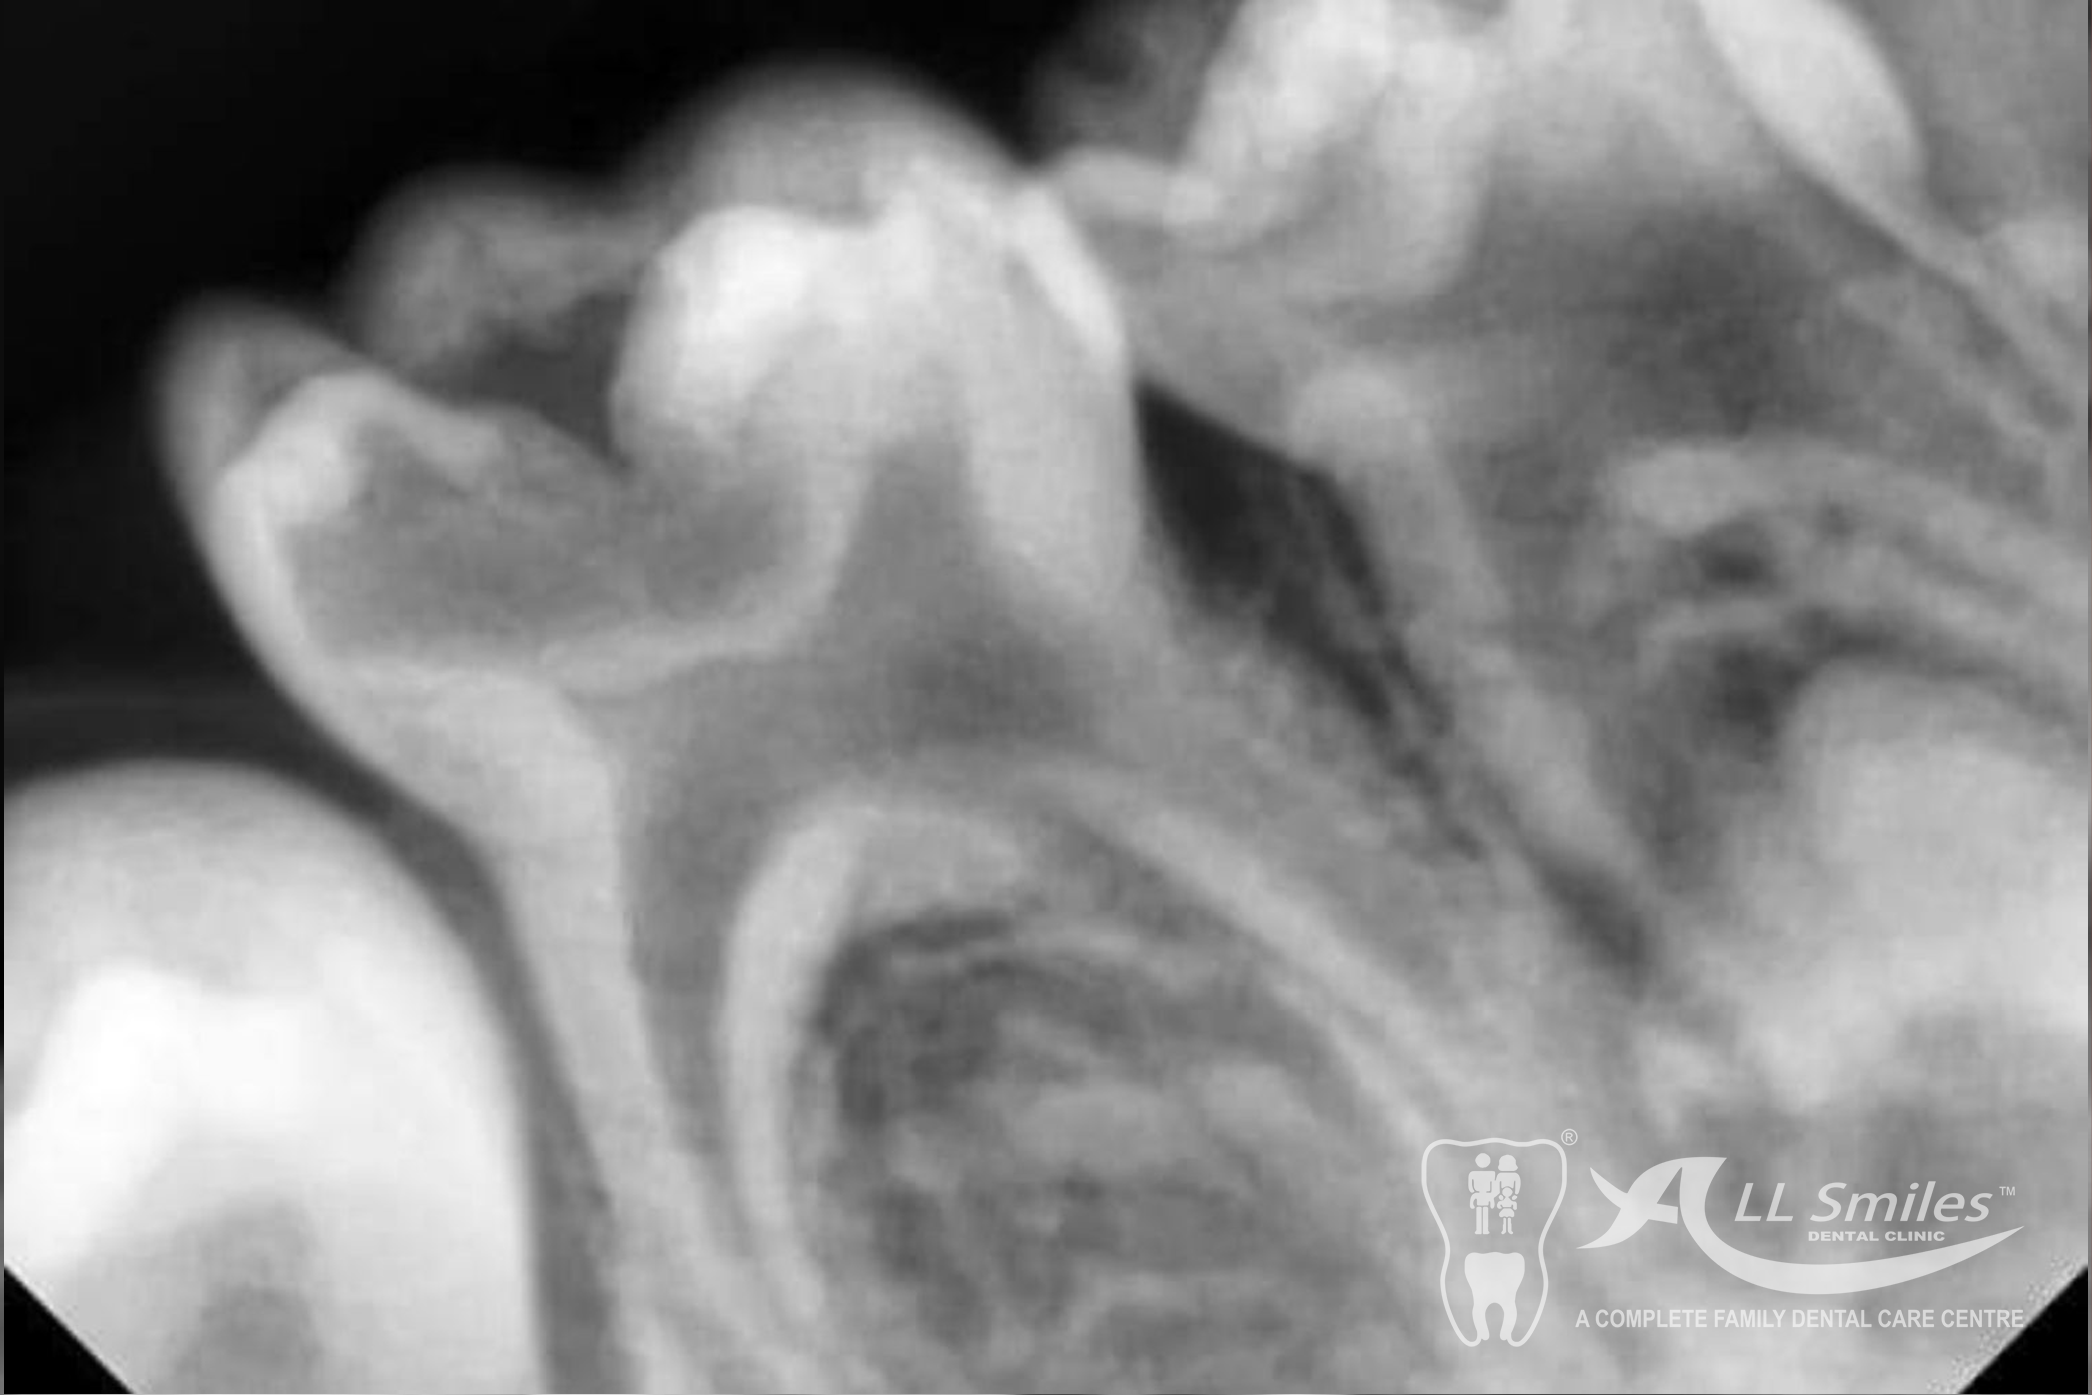

If a child has a cavity, the dentist will remove the decayed portion of the tooth and fill the space with a dental filling. Fillings can be made of various materials, such as composite resin or glass ionomer, depending on the specific needs of the child.

These are treatments performed on baby teeth to save them from extensive decay or infection.

Crowns are tooth-shaped caps that cover and protect damaged or weakened teeth. They are commonly used for baby teeth that have extensive decay or are at risk of fracture.

Child Dentistry Gallery

Yes, dental X-rays are generally safe for children. The level of radiation exposure is minimal, and dentists take necessary precautions to minimize radiation and ensure safety.